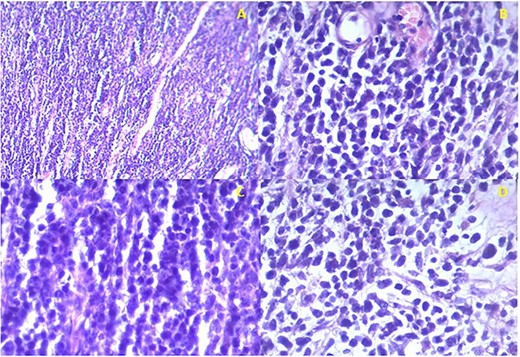

Histology confirmed the presence of a high-grade malignancy. The tissue consisted of fibrous connective tissue and fat. The malignant infiltrate was composed of plump epithelioid cells and occasional spindle cells with pleomorphism. Many of the cells had eosinophilic cytoplasmic inclusions that appeared rhabdoid. Nucleoli, mitotic figures and necrosis were noted (Fig. 2). The histological features favored sarcoma with rhabdoid morphology with a provisional diagnosis of embryonal RMS. The patient was referred to the national cancer institute for further management where he expired before any intervention.

Istopathological analysis. (a) There is densely cellular tumor infiltrates without any discernable pattern. The intercellular matrix consists of sparse fibrous tissue. (b) The majority of the tumor cells appear undifferentiated with hyperchromatic oval to round nuclei with scant cytoplasm. Most of the cells are epithelioid with occasional spindle cells. (c) Occasional mitotic figures are seen. (d) Some cells have eccentric nuclei and abundant pink cytoplasm typical of rhabdomyoblasts.